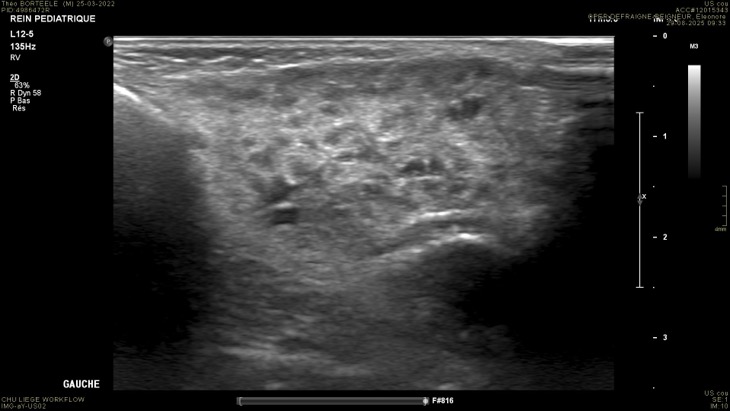

2. PAROTIDITE CHRONIQUE

- Tuméfaction

- Nodules hypo (ganglions intra)

- Hypervascularisation